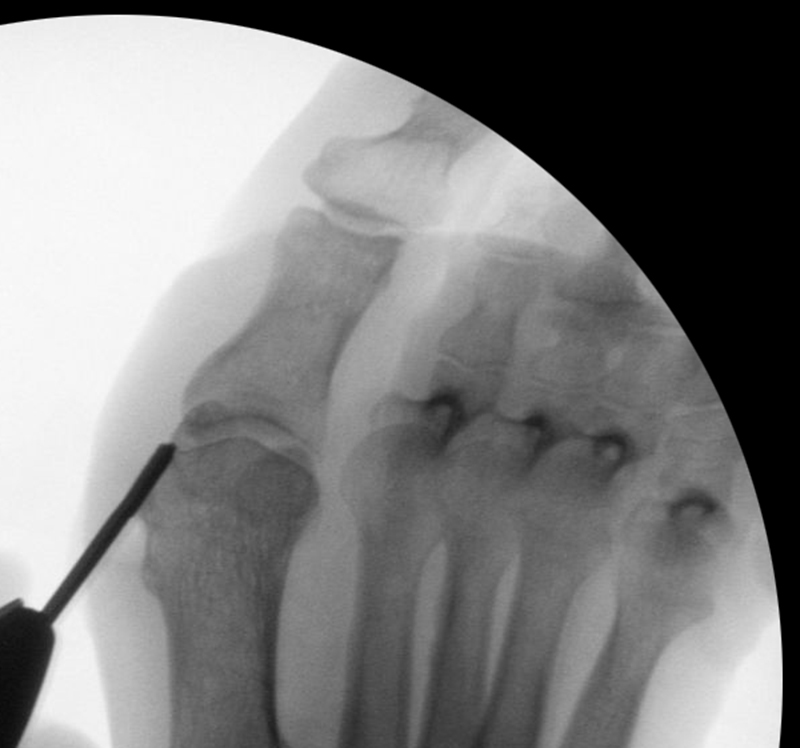

• Bildverstärker für intraoperative Kontrollaufnahmen 3.

• Bildverstärker.

• Gegebenenfalls röntgendichte Handschuhe.

• Positionierung des Bildverstärkers im 90° Winkel zur Fußlängsachse (Abbildung 4).